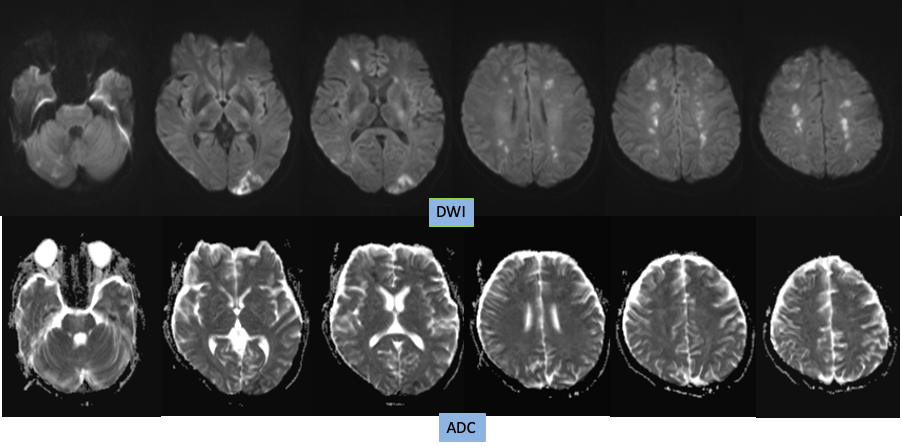

1. 本病例影像学表现提示的诊断线索:青年女性,脑内新见散在多发病灶,散在分布于多个脑动脉供血区,包括幕上幕下,皮层及深部白质,无明显占位效应,病灶周围无水肿,弥散受限,增强扫描左枕叶较大病灶不均匀强化,余病灶无明显强化。

典型影像学表现:DWI 上病灶累及 3 个或 3 个以上血管分布区,常累及前后循环,双侧多见。排除其他明确的栓塞源或与这些病变相关的其他疾病。

多个血管分布区域的梗死:2 分